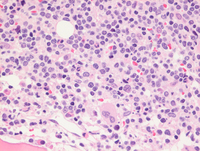

Core biopsy

The bone marrow is extensively involved by dense neoplastic lymphoid infiltrate dispersed interstitially in hypocellular areas and packed in the hypercellular areas. The lymphoma cells are intermediate in size with slightly irregular nuclei, dispersed chromatin, variably distinct nucleoli and scant cytoplasm. Mitotic activity can be readily appreciated. Residual hematopoiesis is markedly reduced on this preparation.